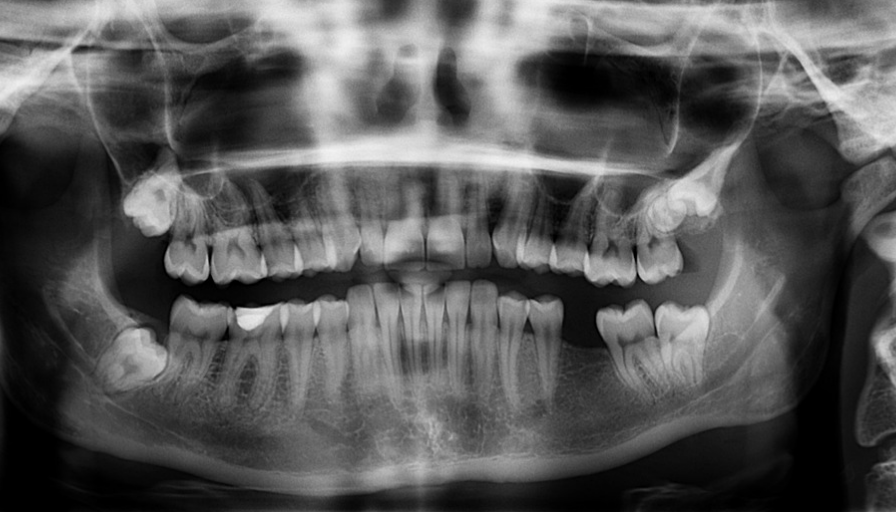

- 구강 및 치아 이상: 치아나 구강 부분의 이상은 이갈이의 원인이 될 수 있습니다. 이상적인 치아 정렬이나 특정한 구강 질환은 이갈이를 유발할 수 있습니다.

- 3.1 치과 진찰과 프로페셔널한 도움

- 이갈이의 원인을 파악하기 위해 정기적인 치과 진찰이 중요합니다.

- 전문가의 조언을 듣고 적절한 치료 및 예방 방법을 받아보세요.